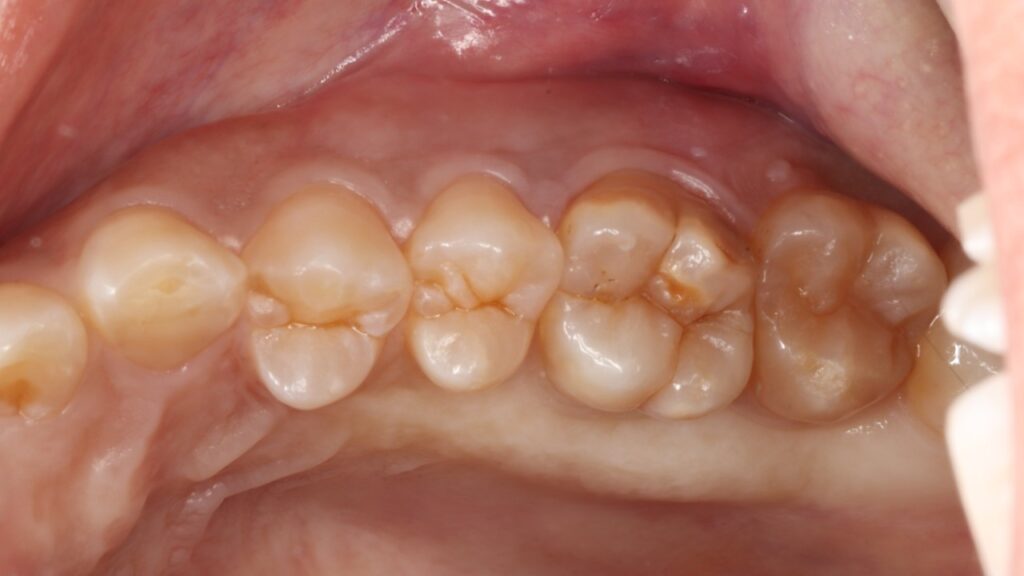

虫歯も歯周病もなく、一見何の問題もないように見えましたがマイクロスコープ(顕微鏡)で詳しく確認すると噛む力に歯が負けて真っ二つに割れてしまっていました。

このように健康な歯が真っ二つに割れることはめったにないのですが、こうなると神経に触る様な強い痛みが出ますし、CTスキャンをとると上顎洞炎にもなっていました。